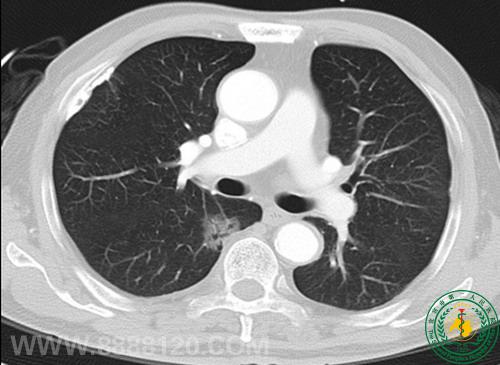

病例75病员诉胸闷,无胸痛。

DR示双侧胸膜钙化,CT示右肺下叶背段磨玻璃密度结节,疑为肺Ca,不完全除外感染性病变。肺穿刺少许组织送病检:结果为肺泡细胞癌。